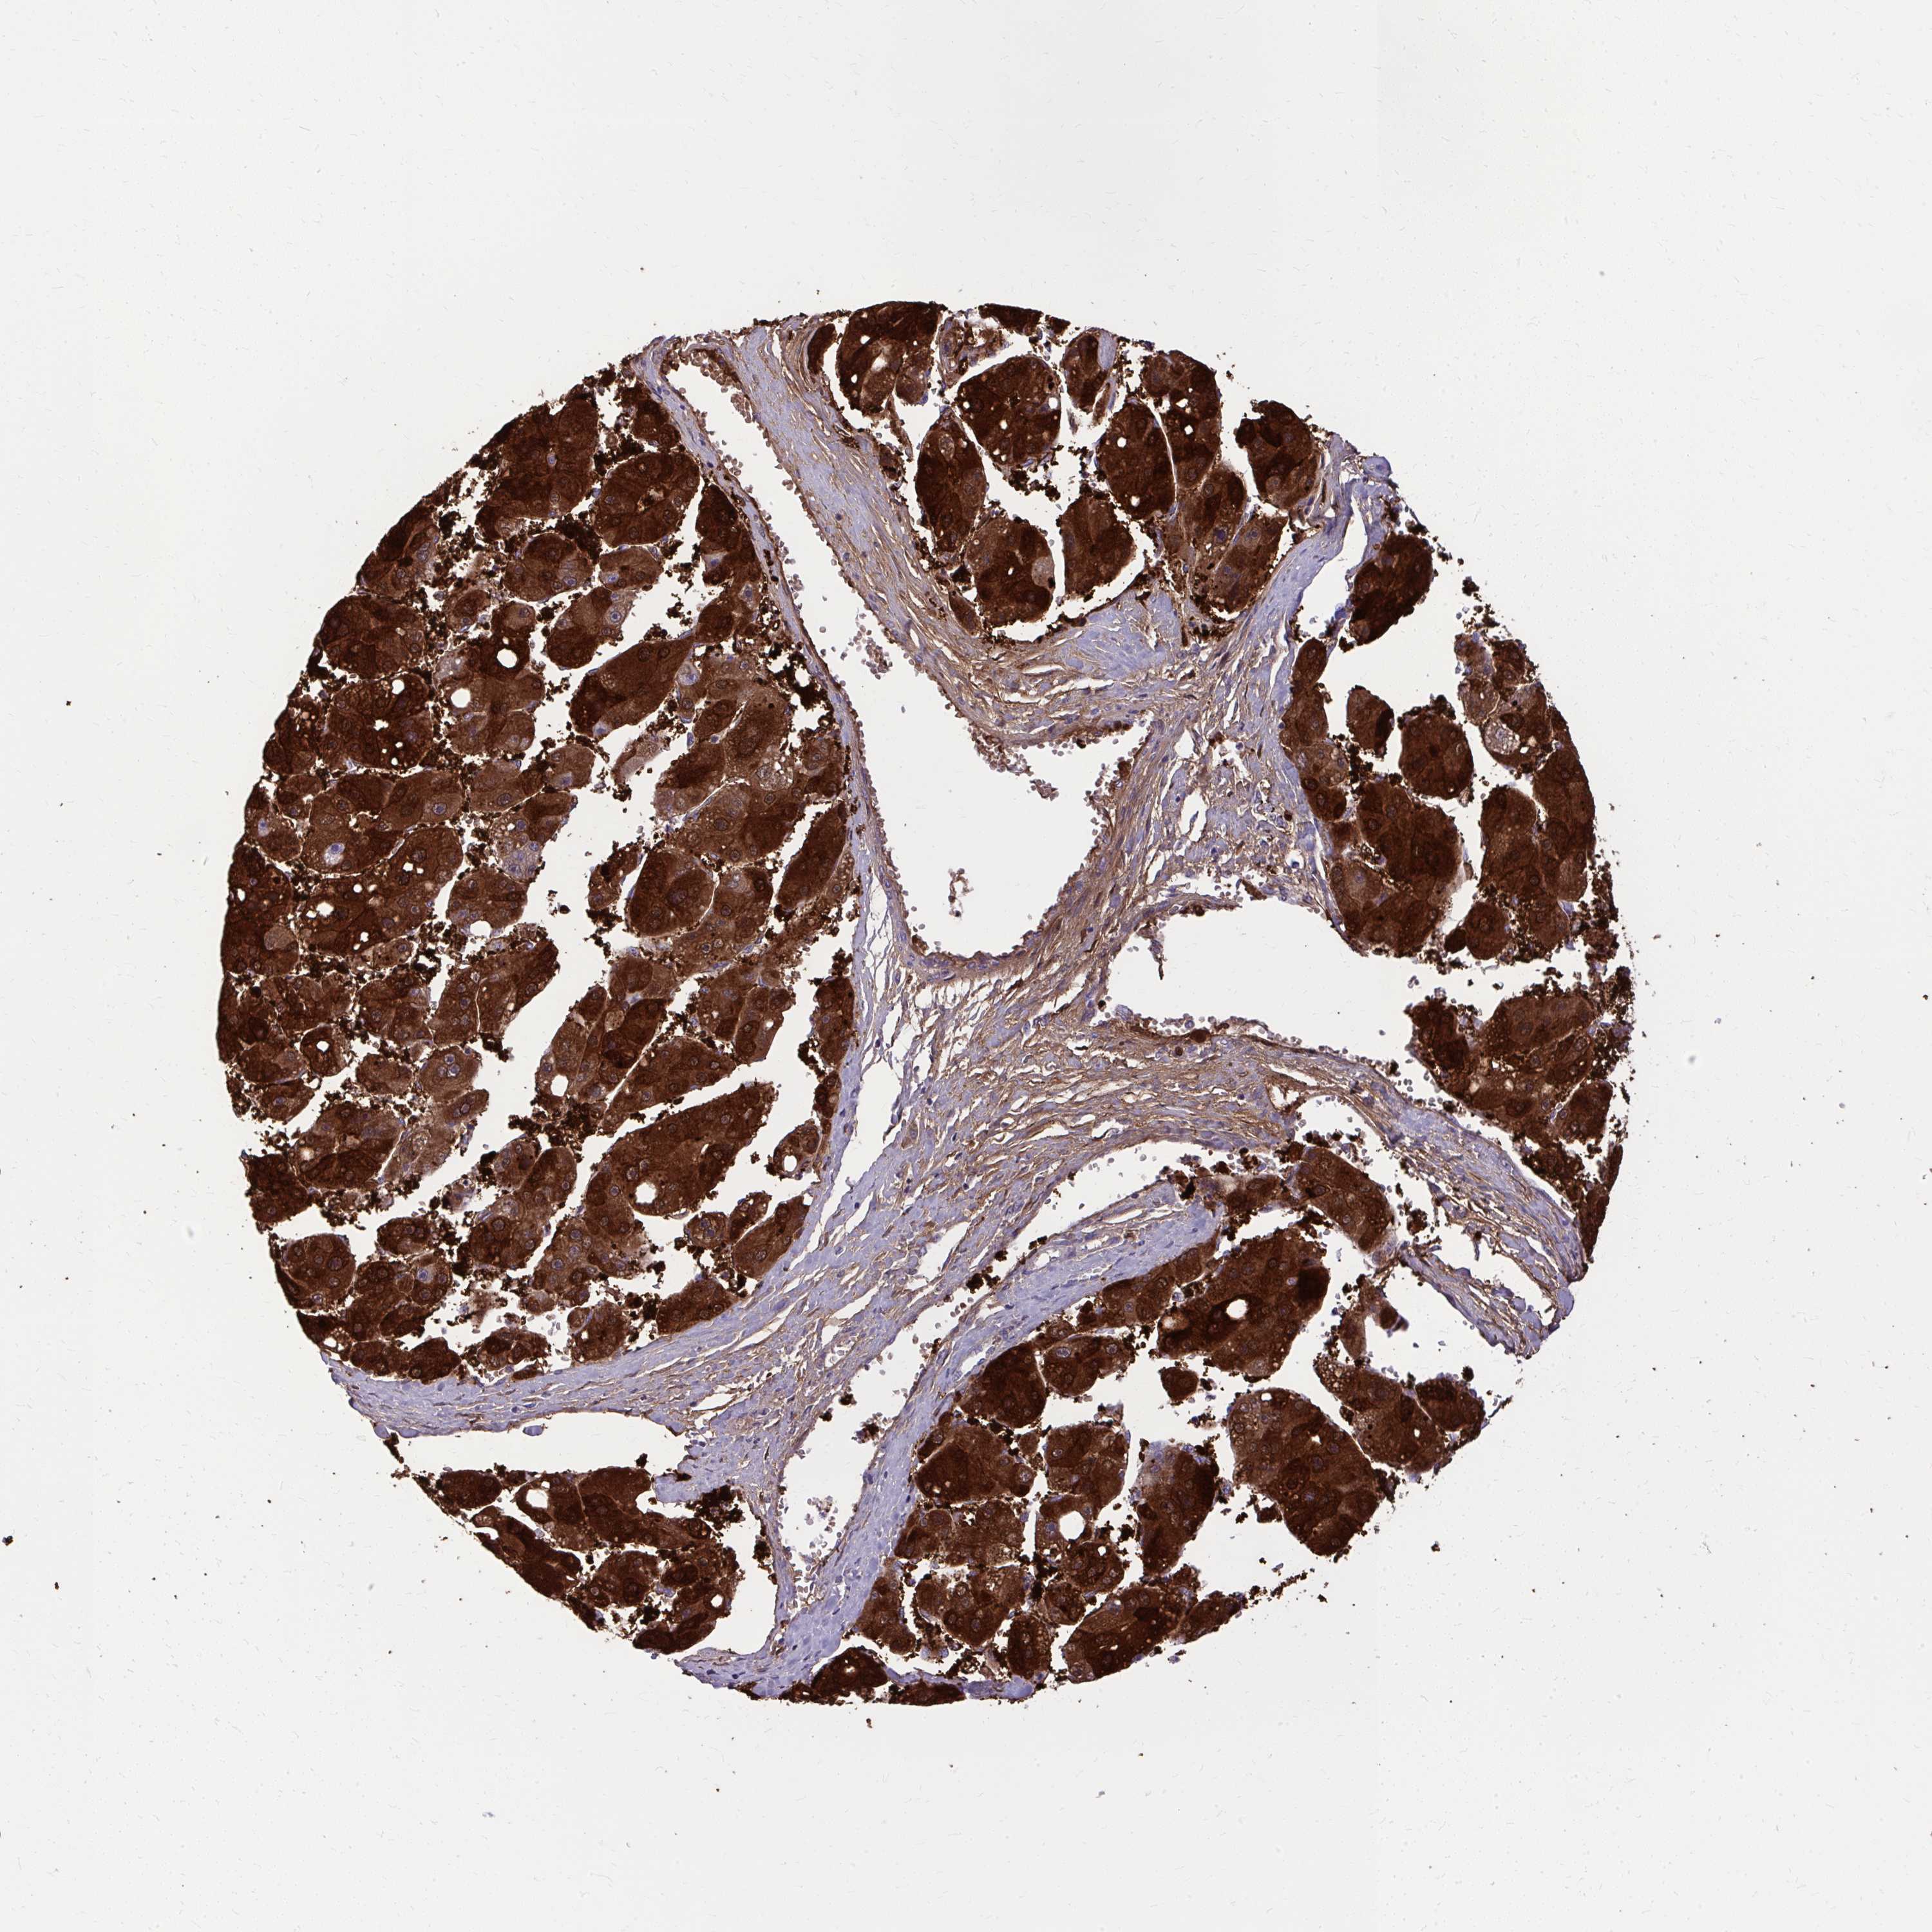

LIVER CANCER - Protein expressioni

A mouse-over function shows sample information and annotation data. Click on an image to view it in a full screen mode. Samples can be filtered based on level of antibody staining by selecting one or several of the following categories: high, medium, low and not detected. The assay and annotation is described here.

Note that samples used for immunohistochemistry by the Human Protein Atlas do not correspond to samples in the TCGA dataset.

Antibody stainingi

Antibody staining in the annotated cell types in the current human tissue is reported as not detected, low, medium, or high, based on conventional immunohistochemistry profiling in selected tissues. This score is based on the combination of the staining intensity and fraction of stained cells.

Each image is clickable and will lead to virtual microscopy that enables deeper exploration of all samples and also displays staining intensity scores, fraction scores and subcellular localization as well as patient and tissue information for each sample.

Antibody HPA059180

Staining

High

Medium

Low

Not detected

Intensity

Strong

Moderate

Weak

Negative

Quantity

>75%

75%-25%

<25%

None

Location

Nuclear

Cytoplasmic/membranous

Cytoplasmic/membranous,nuclear

Carcinoma, Hepatocellular, NOS

Cholangiocarcinoma